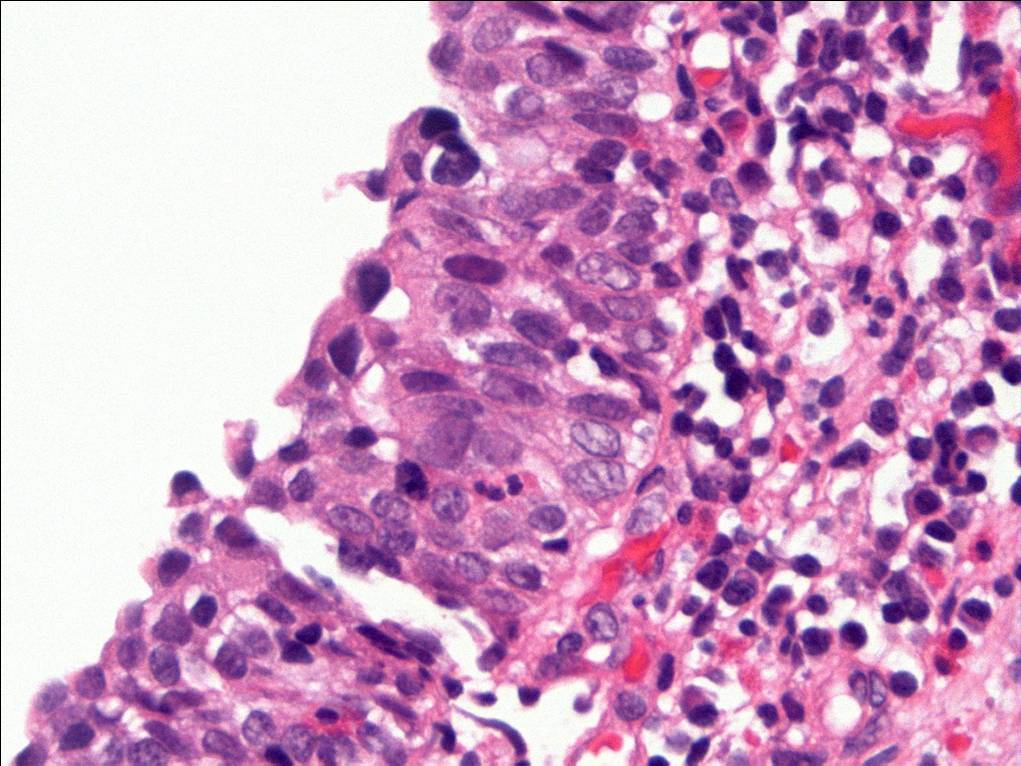

Consensus grade: Carcinoma in situ (CIS)

Case description (by case creator):

The degree of cytologic atypia and loss of polarity is disproportionate to the inflammation present in the lamina propria and the degree of atypia is greater than would be acceptable for reactive atypia.